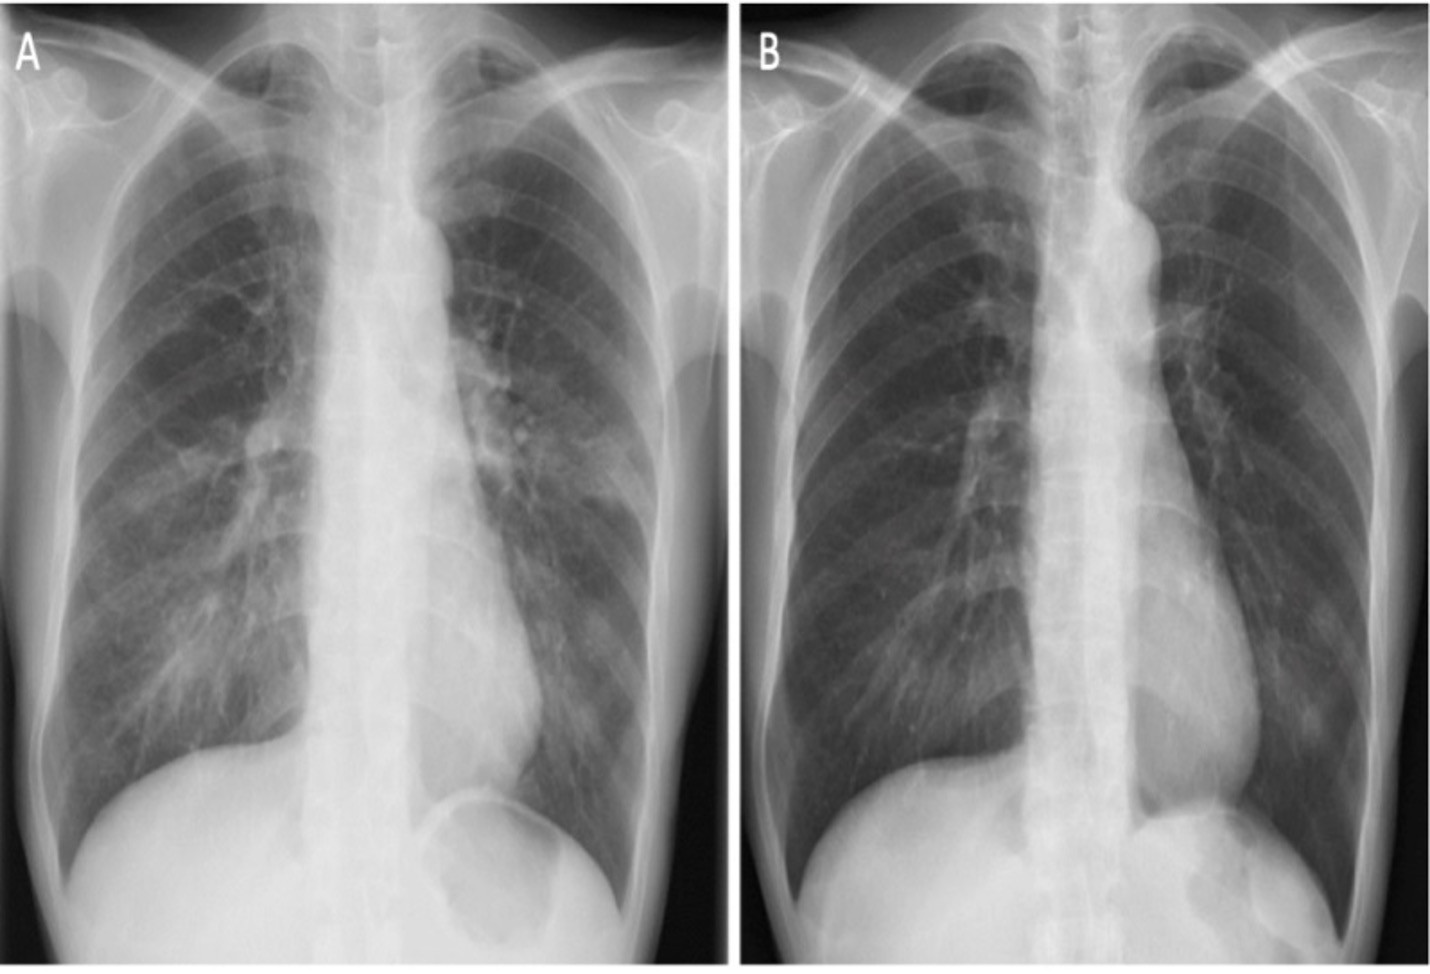

Ung thư phổi - chiếm 12,4% số ca ung thư